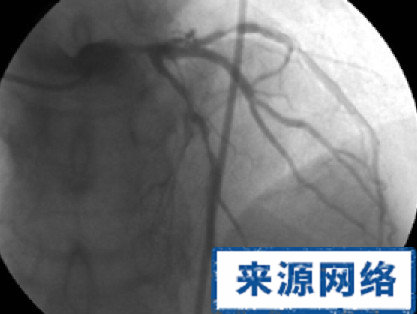

胸悶、胸痛是病情復發的危險信號。若介入後一個月內出現此症狀,要考慮有否血栓形成。半年內出現胸悶、胸痛,尤其是與以前發病時的症狀相似,應高度懷疑發生了再狹窄(即放支架的部位又狹窄了)。一旦出現這類症狀,患者需再次入院復查冠脈造影。